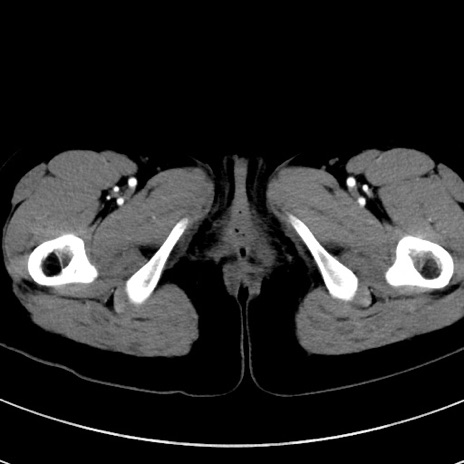

症例17(横断像)

【症例】20歳代女性

【主訴】嘔吐、下腹部痛

【現病歴】昨日夕食後に嘔吐し下腹部痛が出現。本日になっても嘔吐持続し改善しないため来院。

【身体所見】意識清明、BT 37.2℃、BP 108/67mmHg、腹部:平坦、やや硬、下腹部正中から右にかけて圧痛あり、反跳痛軽度あり、tapping pain(+)。

【データ】WBC 13600、CRP 14.94